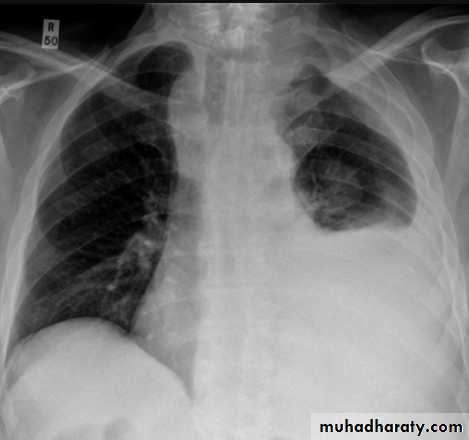

Plain radiographChest radiographs are the most commonly used examination to assess for presence of a pleural effusion, however it should be noted that on a routine erect chest x-ray as much as 250-600 ml of fluid is required before it becomes evident 6. A lateral decubitus film is most sensitive, able to identify even a small amount of fluid. At the other extreme, supine films can mask large quantities of fluid.

Both PA and AP erect films are insensitive to small amounts of fluid. Features include:

blunting of the costophrenic angle

blunting of the cardiophrenic angle

fluid within the horizontal or oblique fissures

eventually a meniscus will be seen, on frontal films seen laterally and gently sloping medially (note:

with large volume effusions, mediastinal shift occurs away from the effusion (note: if coexistent collapse dominates then mediastinal shift may occur towards the effusion)